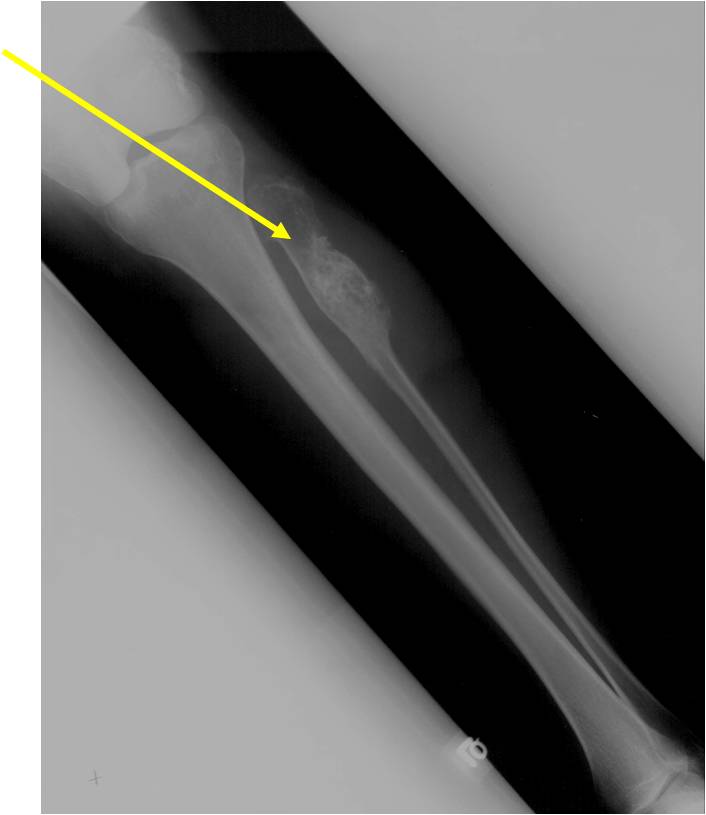

Metaphyseal Tumor, Heavy Calcifications, Ring and Arc Pattern of Calcifications, Minimal Endosteal Scalloping, No Cortical Destruction, No Periosteal Reaction, No Cortical Destruction, No Soft Tissue Component

Metaphyseal Tumor, Heavy Calcifications, Ring and Arc Pattern of Calcifications, Minimal Endosteal Scalloping, No Cortical Destruction, No Periosteal Reaction, No Soft Tissue Component